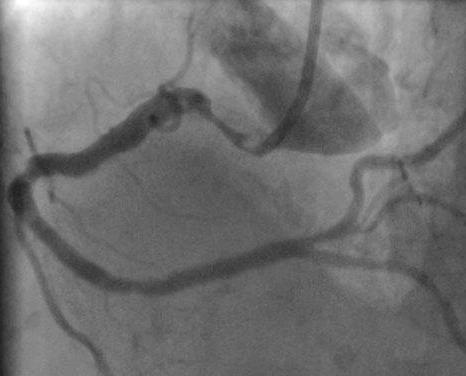

One or more bends of 90° or more, or three or more bends of 45° to 90° proximal of the diseased segment.